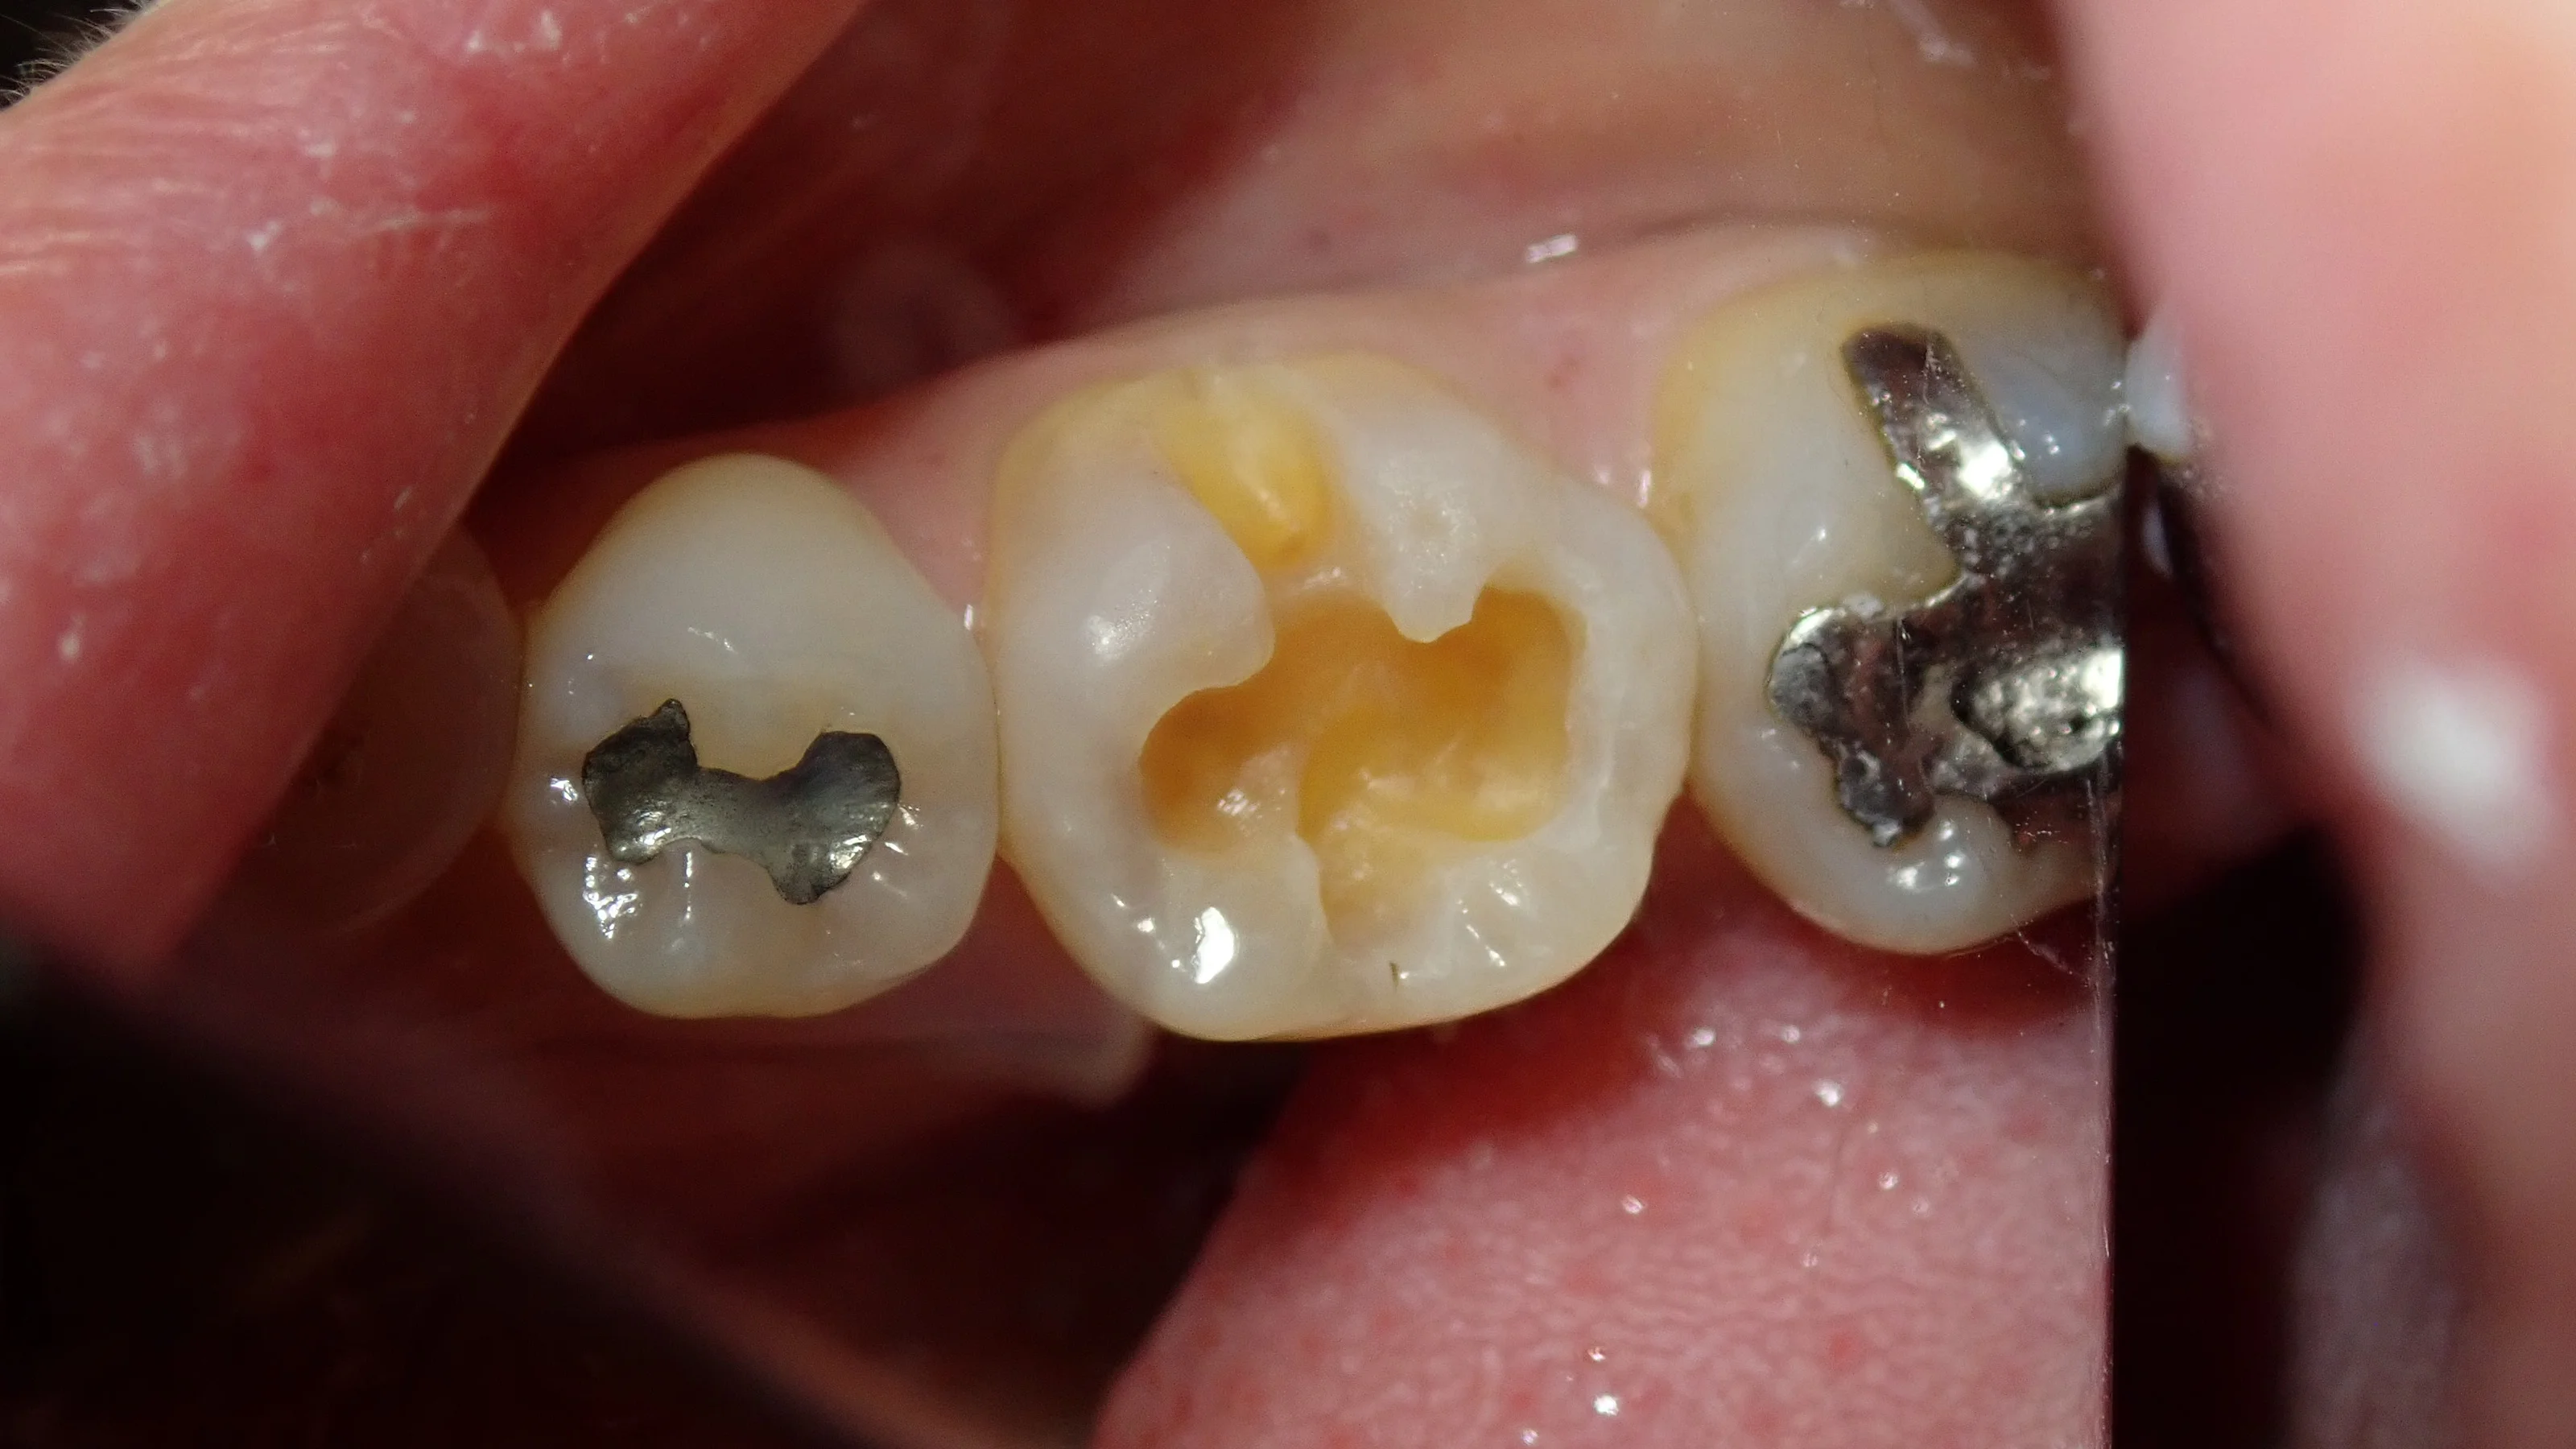

詰め物だけ外してみると、所々黒く、柔らかくなっており、 虫歯になっているのが分かりやすい状況でした。

で、虫歯を取り切った状態がこちらです。

コンポジットレジン|坂寄歯科医院(取手市藤代) - 画像3

写真での影で分かると思いますが、結構深かったです。

ただ、咬頭(かみ合わせの一番強くかかる場所)は全て残存しており、歯としてはしっかりと残せています。